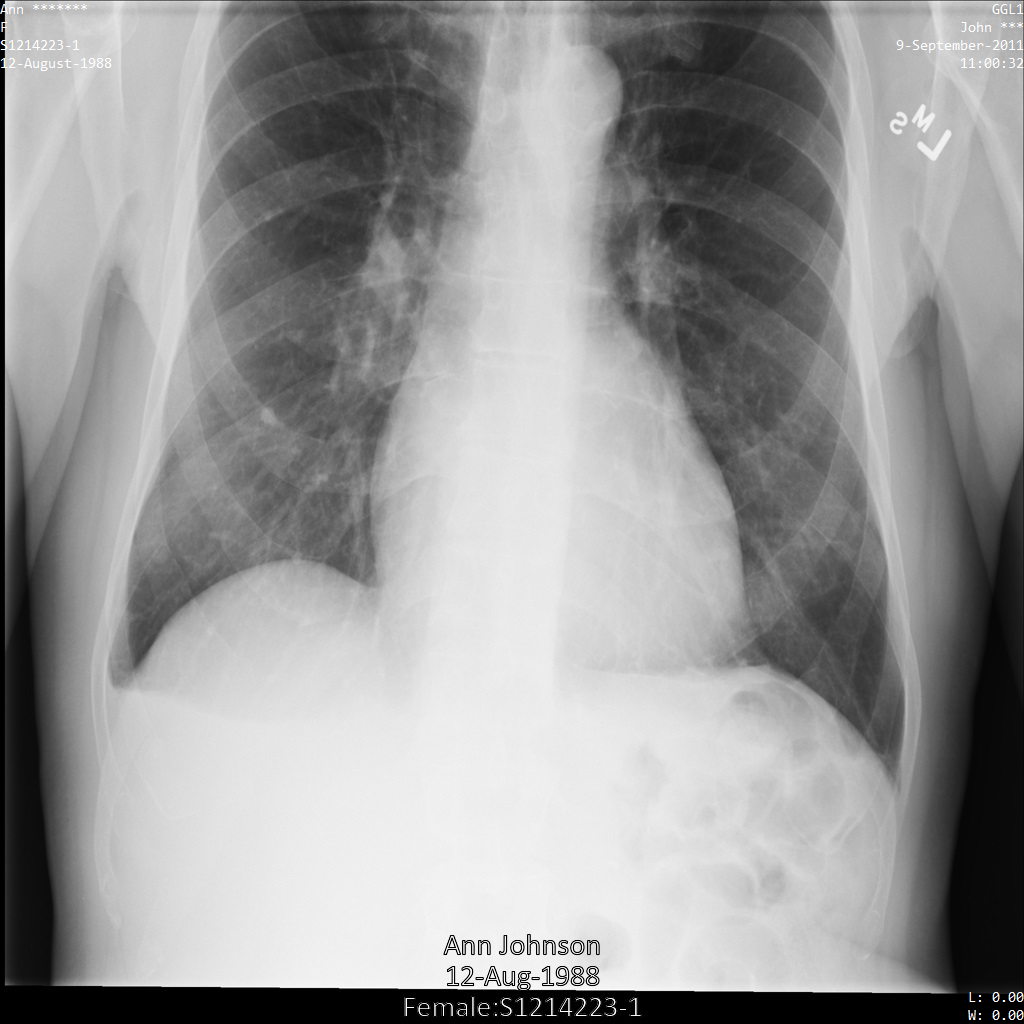

A imagem seguinte mostra uma radiografia não ocultada de um paciente:

Depois de enviar a imagem para a Cloud Healthcare API através da opção REDACT_SENSITIVE_TEXT, a imagem é apresentada da seguinte forma:

Pode ver que ocorreu o seguinte:

- O

PERSON_NAMEna parte inferior esquerda da imagem foi ocultado - O

DATEna parte inferior esquerda da imagem foi ocultado

O sexo do paciente não foi ocultado porque não é considerado texto sensível de acordo com os infoTypes DICOM predefinidos.